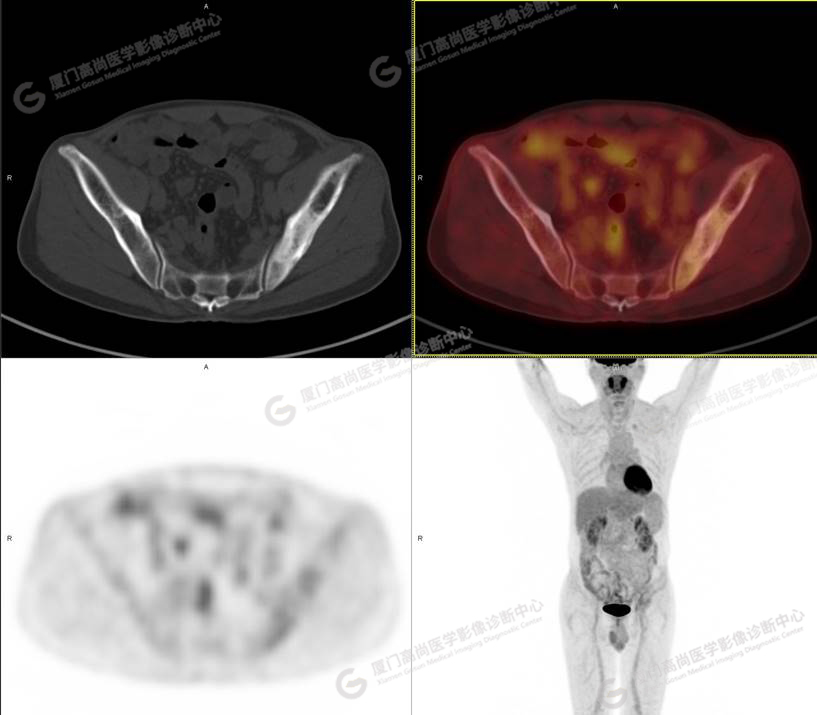

病史摘要1

60歲的L先生,因“左側(cè)臀部疼痛伴行走困難3月余”就診,外院核素骨顯像示:左側(cè)髂骨顯像劑增加,考慮惡性病變可能。同時實驗室檢查發(fā)現(xiàn)腫瘤指標(biāo)糖類抗原724稍增高。談癌色變!驚恐的L先生選擇了腫瘤檢查的核武器——PET/CT以探明虛實。

PET/CT檢查

PET/CT所見:左側(cè)髂骨、髖臼及恥骨骨質(zhì)密度不均勻增高,CT值約594Hu,邊緣模糊,放射性攝取輕度增高,SUVmax 2.79,周圍軟組織未見明顯異常。